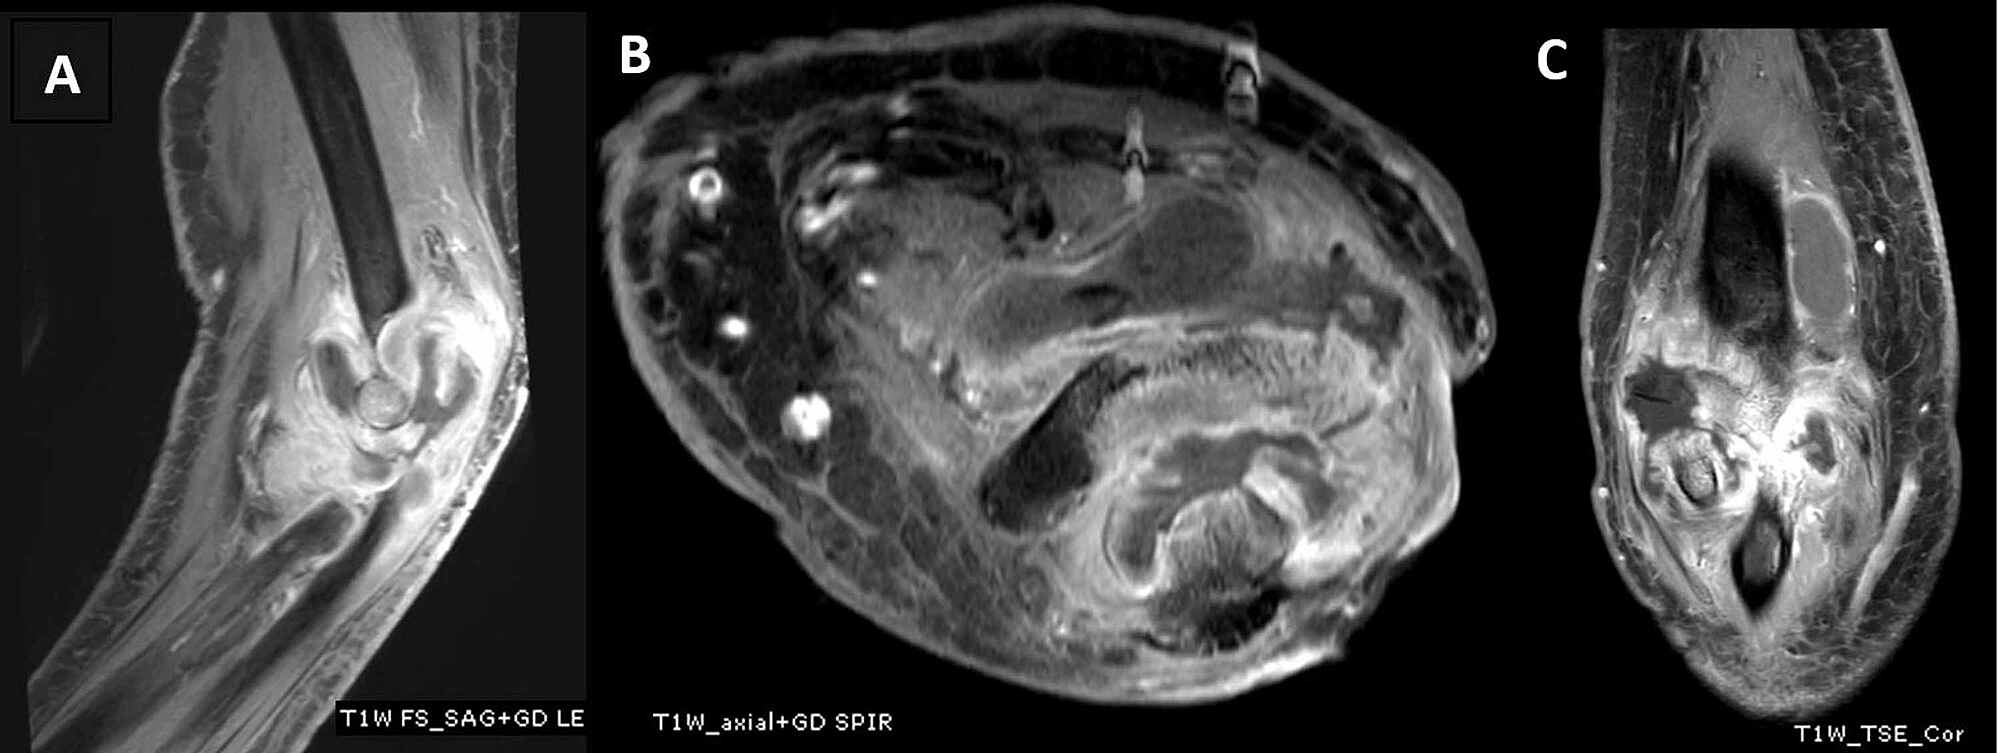

resonance imaging features of large joint tuberculous arthritis Indian Journal of Elbow Arthritis Mri Mri of the elbow is a fairly frequent examination in musculoskeletal radiology practice and not quite as common in general radiological. Rheumatoid arthritis (ra) is a chronic autoimmune multisystemic inflammatory disease that affects many organs but predominantly attacks the synovial tissues. Evaluation of the elbow by magnetic resonance imaging (mri) is an important adjunct to the physical examination. Mr signal. Elbow Arthritis Mri.

resonance imaging findings in tubercular arthritis of elbow Clinical Imaging Elbow Arthritis Mri Rheumatoid arthritis (ra) is a chronic autoimmune multisystemic inflammatory disease that affects many organs but predominantly attacks the synovial tissues. Evaluation of the elbow by magnetic resonance imaging (mri) is an important adjunct to the physical examination. Learn how to diagnose rheumatoid arthritis (ra) using mri findings from a case study and a review of the pathophysiology and. Mri of. Elbow Arthritis Mri.

resonance imaging findings in tubercular arthritis of elbow Clinical Imaging Elbow Arthritis Mri Rheumatoid arthritis (ra) is a chronic autoimmune multisystemic inflammatory disease that affects many organs but predominantly attacks the synovial tissues. Evaluation of the elbow by magnetic resonance imaging (mri) is an important adjunct to the physical examination. This web page covers common types of elbow injuries, such. Learn how to diagnose rheumatoid arthritis (ra) using mri findings from a case. Elbow Arthritis Mri.